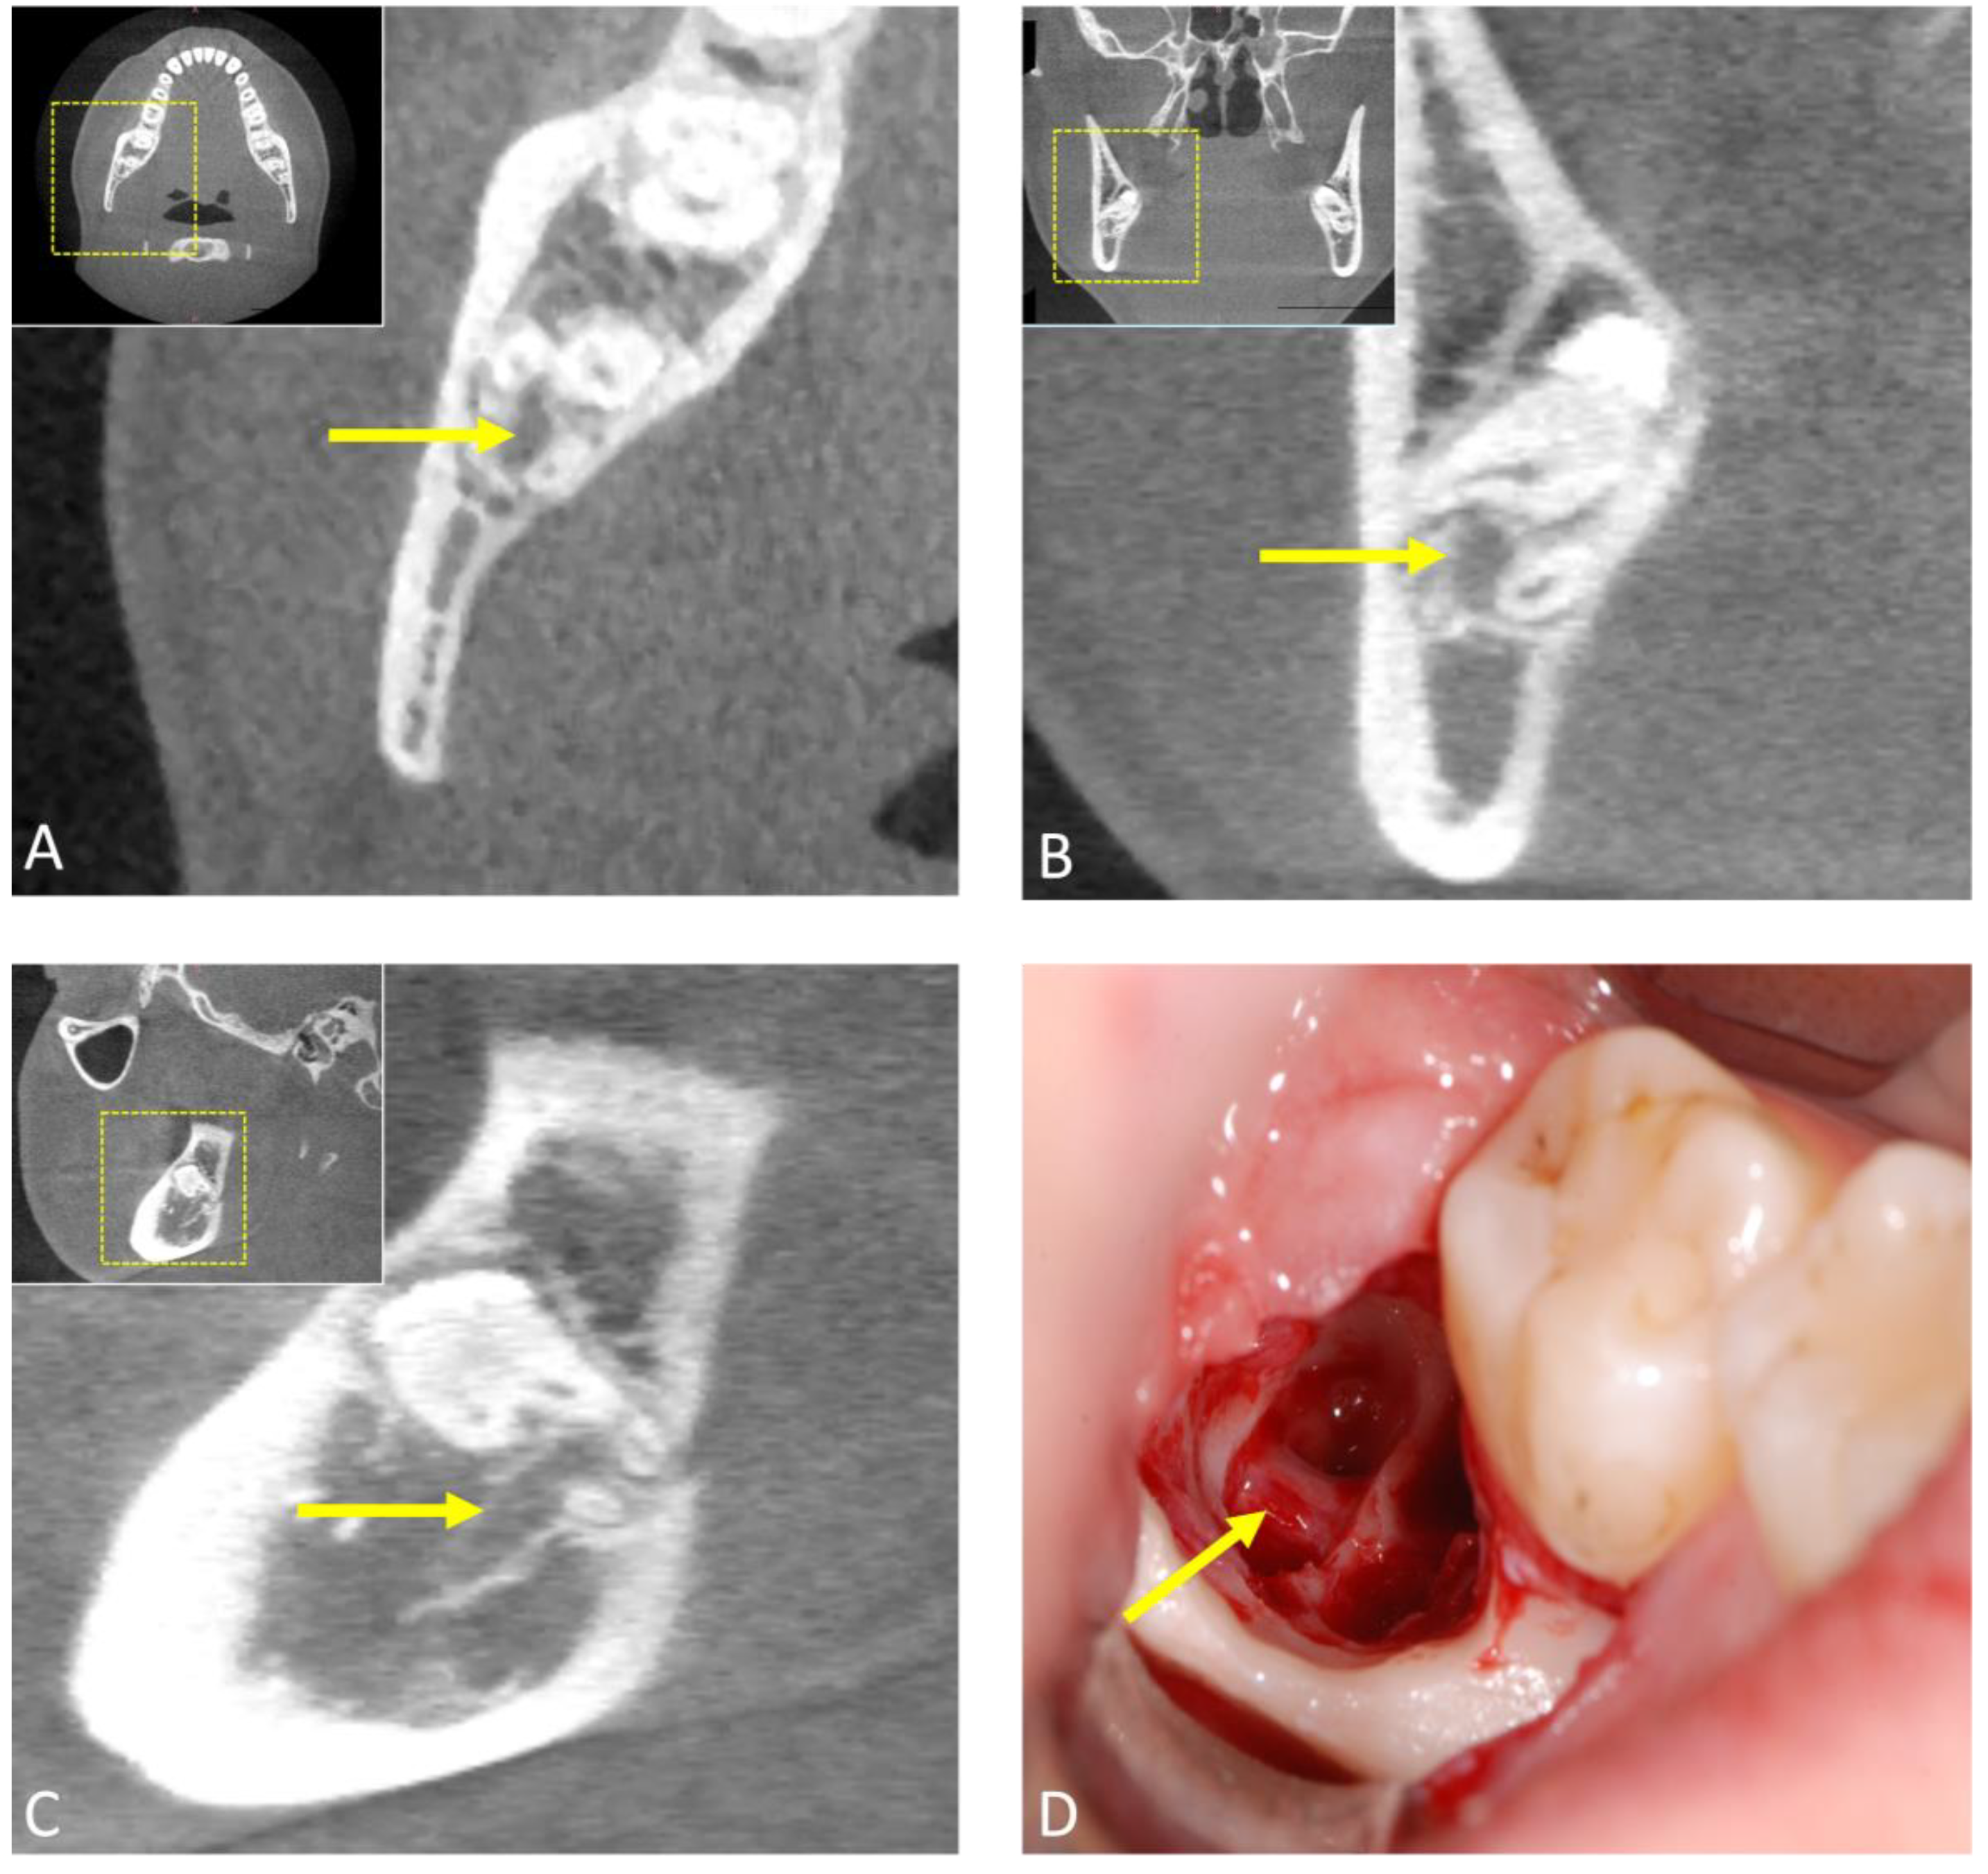

- Nakamori, K.; Tomihara, K.; Noguchi, M. Clinical significance of computed tomography assessment for third molar surgery. World J. Radiol. 2014, 6, 417–423. [Google Scholar] [CrossRef]

- Susarla, S.M.; Dodson, T.B. Preoperative computed tomography imaging in the management of impacted mandibular third molars. J. Oral Maxillofac. Surg. 2007, 65, 83–88. [Google Scholar] [CrossRef]

- Xu, G.Z.; Yang, C.; Fan, X.D.; Yu, C.Q.; Cai, X.Y.; Wang, Y.; He, D. Anatomic relationship between impacted third mandibular molar and the mandibular canal as the risk factor of inferior alveolar nerve injury. Br. J. Oral Maxillofac. Surg. 2013, 51, e215–e219. [Google Scholar] [CrossRef] [PubMed]

- Ohman, A.; Kivijärvi, K.; Blombäck, U.; Flygare, L. Pre-operative radiographic evaluation of lower third molars with computed tomography. Dentomaxillofac. Radiol. 2006, 35, 30–35. [Google Scholar] [CrossRef]

- Lübbers, H.T.; Matthews, F.; Damerau, G.; Kruse, A.L.; Obwegeser, J.A.; Grätz, K.W.; Eyrich, G.K. Anatomy of impacted lower third molars evaluated by computerized tomography: Is there an indication for 3-dimensional imaging? Oral Surg. Oral Med. Oral Pathol. Oral Radiol. Endod. 2011, 111, 547–550. [Google Scholar] [CrossRef]